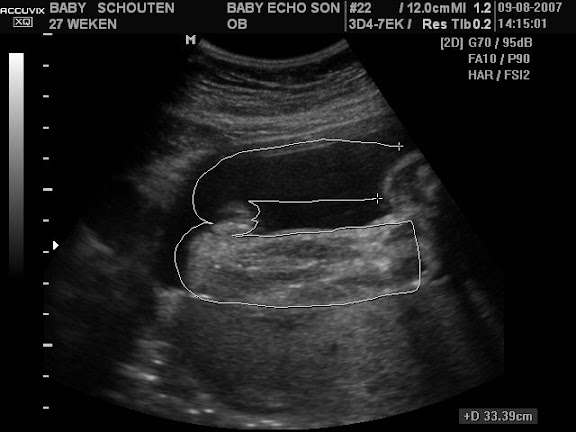

mag ik jullie voorstellen aan onze frutsel

dank je be

Popplesdinsdag 30 oktober 2007 @ 23:13

klein spookje dit is geen pretecho. er zijn meerdere dames van hier geweest in eindhoven daar zoeken ze zwangere vrouwen waar ze op mogen oefenen. vandaar deze foto en ik mag nog 2 keer daar komen voor een echo een pretecho kan verschillen met wat je wilt en waar je woont. misschien even googlen.